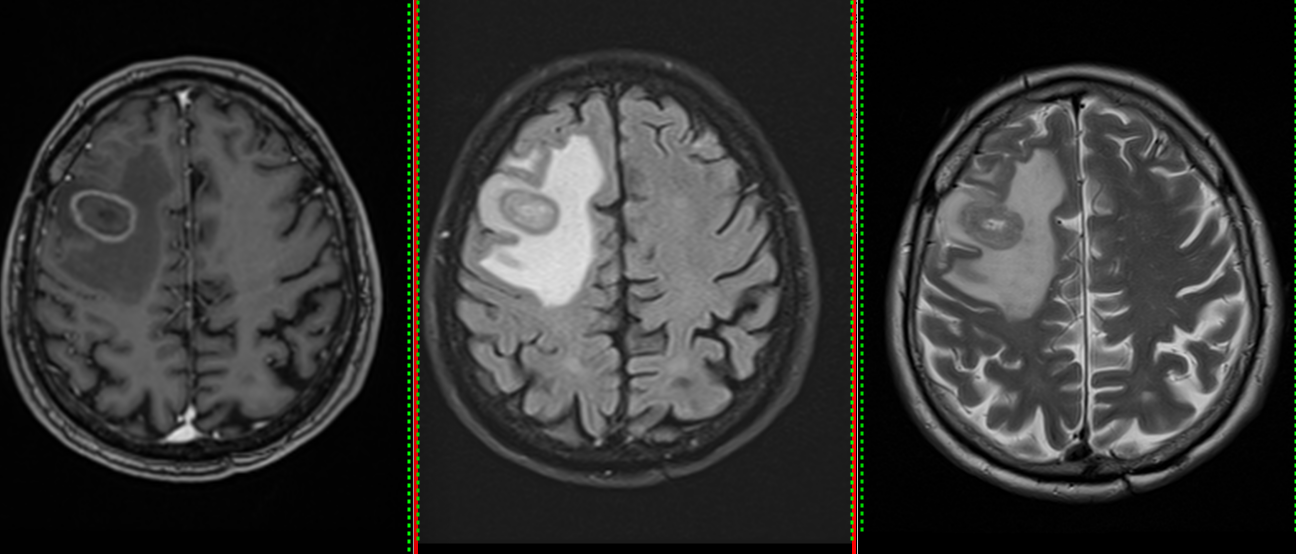

- Imagistică cerebrală: RMN-ul cu substanță de contrast este metoda de elecție, dar și CT-ul poate fi util.

- Radiochirurgia stereotactică (Gamma Knife, CyberKnife) – recomandată pentru metastaze unice sau puține, bine localizate, cu dimensiuni sub 2 cm.

- În mod particular metastazele chistice se pretează la intervenție chirurgicală, având un răspuns slab la radioterapie per primam.

Celulele canceroase se desprind din tumora primară, pătrund în vasele de sânge și călătoresc spre creier. Acolo, ele trec de bariera hemato-encefalică – o structură protectoare care apără creierul de substanțe toxice – și încep să se multiplice. De cele mai multe ori, metastazele apar în zona joncțiunii dintre substanța albă și cea cenușie, unde fluxul sanguin este bogat și viteza de circulație este mai redusă.